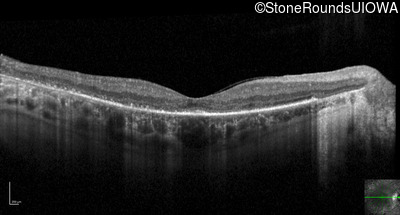

Optical Coherence Tomography - Right - 20/40 -1

Exemplar / OCT Stack

OCT Stack